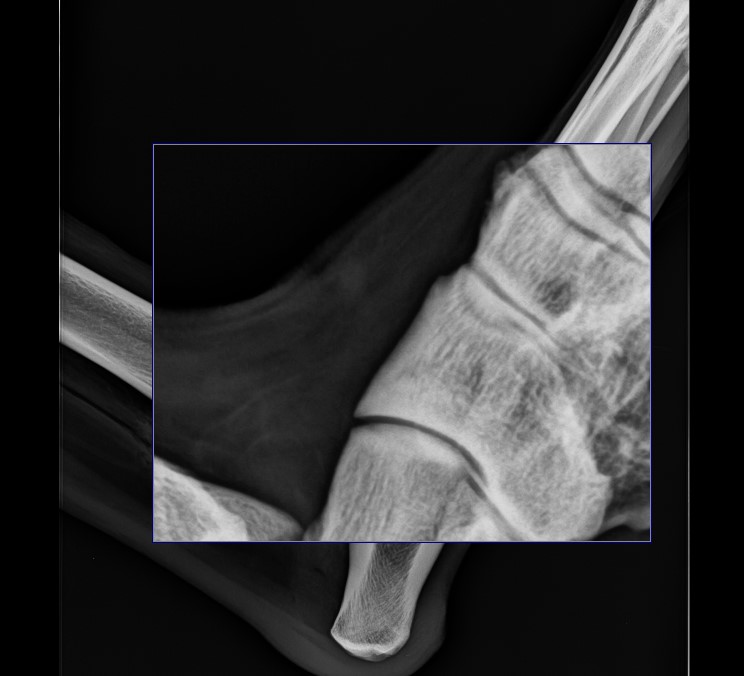

Zoom In¶

To quickly magnify an area of interest use the Zoom In tool from the viewer toolbar. This tool can be assigned to a specific mouse button. By default, the right mouse button is assigned to this tool.

Press and hold on the image with the assigned mouse button to activate the tool and show the zoomed in portion of the image. Move the zoomed in portion of the image by dragging the mouse the desired direction.